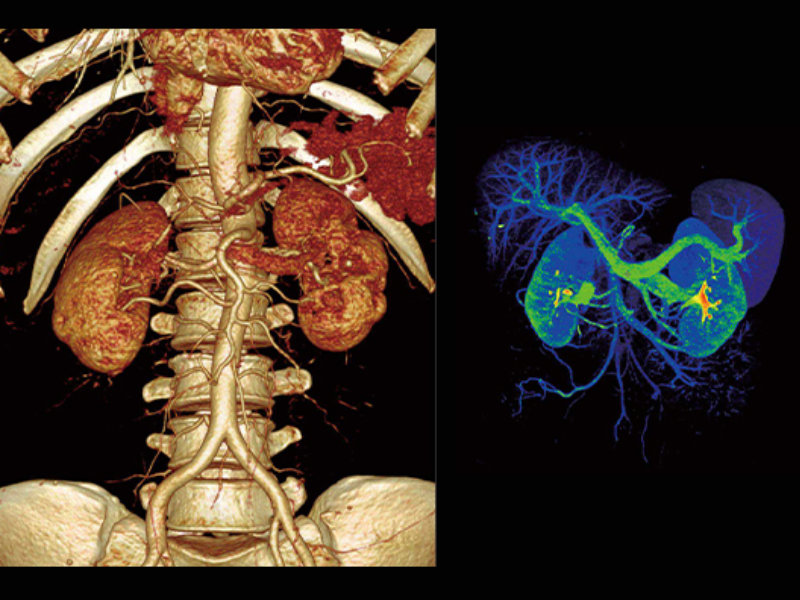

Whole Organ Coverage

160-slice CT with Z-Detector

The ultra-low noise design of the Z-Detector helps produce high image quality with low radiation dose.